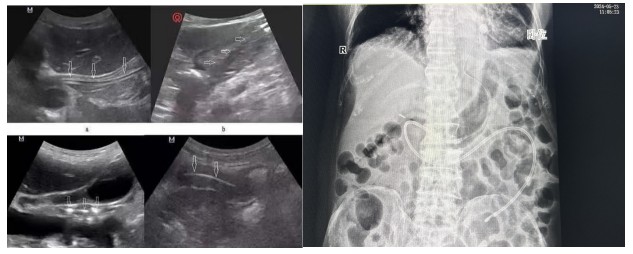

經(jīng)腹部X片驗(yàn)證一個(gè)完美的大“C”呈現(xiàn)出來(lái),確認(rèn)鼻空腸管已經(jīng)達(dá)到指定位置。

B超引導(dǎo)下營(yíng)養(yǎng)管置入術(shù)相比內(nèi)鏡輔助下?tīng)I(yíng)養(yǎng)管置入,通過(guò)二維顯像觀察鼻腸管的位置,無(wú)創(chuàng)監(jiān)測(cè),定位準(zhǔn)確,提高了置管的成功率,能有效減少置管給病人帶來(lái)的不適體驗(yàn)及不必要的損傷。營(yíng)養(yǎng)支持已成為重癥患者綜合治療重要環(huán)節(jié),對(duì)重癥患者預(yù)后起著關(guān)鍵作用,新喂養(yǎng)途徑的建立,讓腸內(nèi)營(yíng)養(yǎng)支持順利的開(kāi)展,不僅減少了患者的痛苦,也為重癥營(yíng)養(yǎng)支持治療開(kāi)辟了一條嶄新的補(bǔ)給通道。